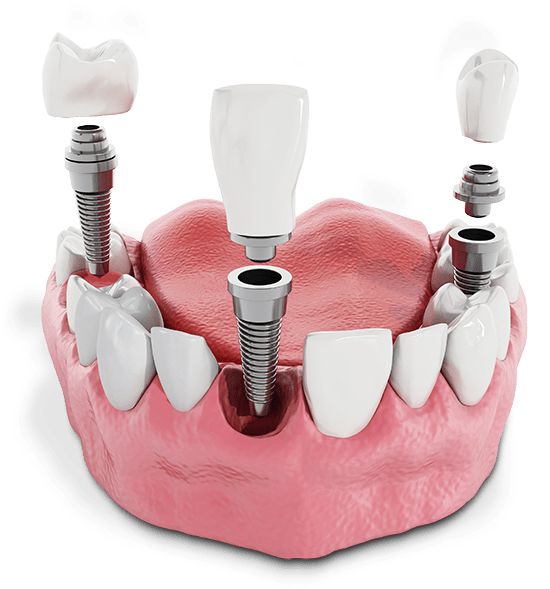

Dental implants are made up of three parts that work together to replicate the function of natural teeth. The artificial tooth called a crown is anchored to your jawbone via a surgically implanted titanium post. A small metal piece called an abutment connects the post to the crown, either as a separate piece or built into the post.

Once new bone grows around the implant post, it assumes the role of the missing tooth root, providing stable and strong support for a crown, bridge, or full-mouth dental implant. With extensive expertise and technology, our team can help you experience improved health, function, and confidence with dental implants in Edmond, OK!

Secured in the jawbone, dental implants can replace any number of missing teeth while fully restoring function and aesthetics. With advances in implant technology, you have many tooth replacement options to choose from today.

Single dental implants, implant-supported bridges, removable or fixed implant-supported dentures, and full-mouth dental implants are long-lasting alternatives to traditional options. For single implants, CEREC® technology enables creating a crown on-site with our specialized milling machine, after proper healing and fusion with the underlying bone has occurred.